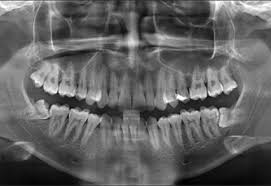

Panoramic Dental X Ray Showing A Crowding With A 10 Years Old Child Characterized By The Overlapping Of The Inciso Wisdom Teeth Wisdom Tooth Extraction Dental